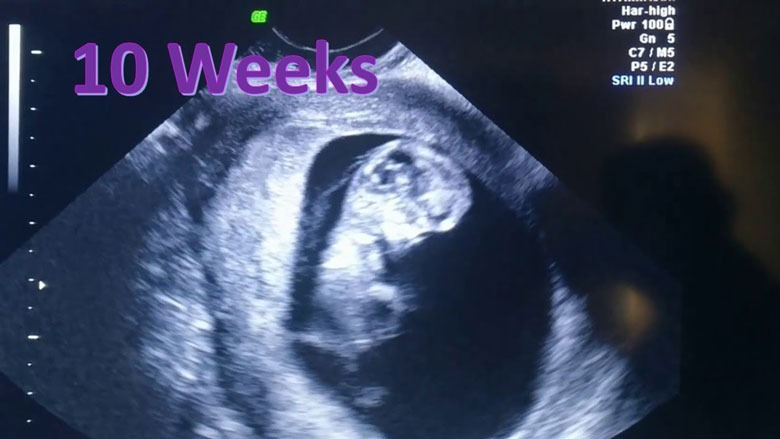

Quá trình phát triển thai nhi 10 tuần tuổi là một trong những dấu mốc quan trọng trong thời kỳ mang thai. Vào giai đoạn này, các nơron thần kinh bắt đầu phát triển với tốc độ nhanh chóng, đồng thời tế bào não bộ giúp cải thiện chức năng quản lý và điều khiển hoạt động của toàn cơ thể. Kích thước của bé yêu lúc này là khoảng 3.1cm, nặng 4g, tương đương với một quả mận. Nhịp tim thai 10 tuần tuổi ở trạng thái bình thường là từ 120-160 lần/phút.

Bên cạnh đó, hình ảnh thai nhi tuần thứ 10 khi siêu âm còn cho thấy những cử động dễ dàng, linh hoạt của bé như xoay, đạp; bởi lúc này, hệ thống xương khớp đã được xây dựng hoàn chỉnh hơn, đặc biệt là cấu trúc các sụn xương phát triển vững chắc. Sang tuần thứ 10 của thai kỳ, các răng sữa vẫn tiếp tục được hình thành và được gắn chặt với khớp hàm. Hệ thống tiêu hóa và bài tiết hoạt động mạnh mẽ hơn do các nội tiết tố đang trong giai đoạn sắp xếp và tổng hợp để hoàn thiện chức năng của mình.

Bộ phận sinh dục của thai nhi ở tuần này chưa lộ rõ, vì vậy bác sĩ và mẹ gần như chưa thể biết được chính xác giới tính thai nhi. Những mẹ bầu thường thắc mắc thai 10 tuần tuổi đã biết trai hay gái chưa không nên quá sốt ruột, hãy kiên nhẫn chờ đợi thêm một vài tuần nữa.